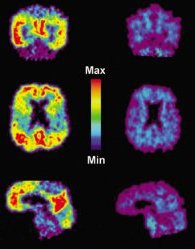

Recent advances in brain imaging have increased the reliability of diagnosing full-blown Alzheimer’s in a living person. But the brain’s biology begins to go haywire long before symptoms of serious mental decline or outright Alzheimer’s become evident. And it’s still a challenge to distinguish someone on track to developing Alzheimer’s from someone who is aging normally—much less treating that individual to slow or stop the disease process.